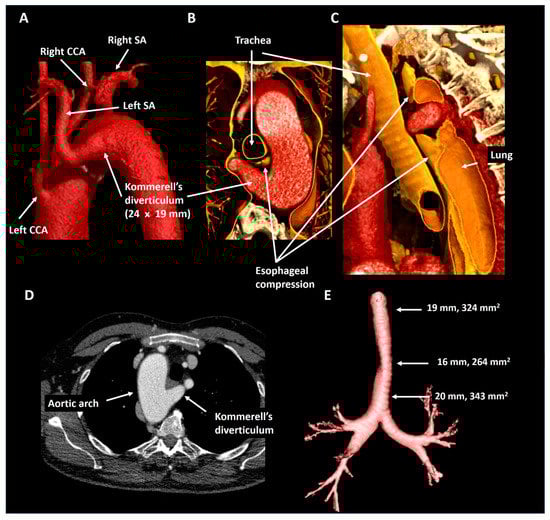

2.6. Patient 6

| Patient 6 | 23 | Male | Right-sided arch, mirror imaging branching and KD | Mild tracheal and esophageal compression | 27 × 21 mm, 440 mm2 | Dyspnea, although excellent objective exercise capacity | Structural imaging follow-up |